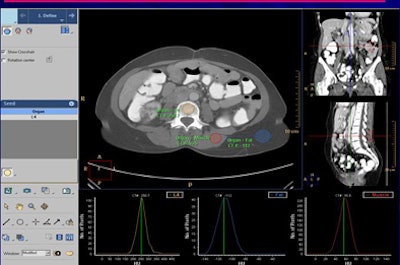

| Above and below, graphic user interface for bone mineral density software (BMAP, Philips) shows analysis of trabecular bone (marked by circular region of interest in pink) from normally acquired CTC datasets. The software plots a histogram from the region of interest to calculate peak bone mineral density value, representing the attenuation value that occurs most frequently. Tricolor map at bottom right represents three bone mineral density ranges for patients, with the topmost stripe in green representing normal bone mineral density. Black point in yellow stripe indicates a patient at risk of osteoporosis or osteopenia based on the analysis of three trabecular bone facets. All images courtesy of Dr. Rizwan Aslam. |